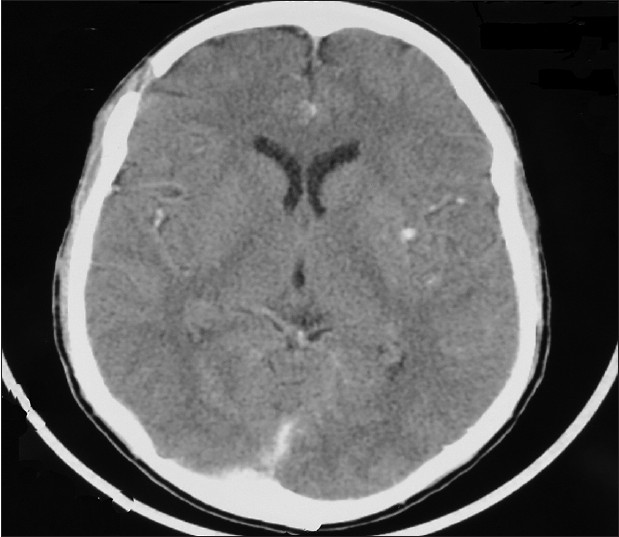

We report a case of an 18-year-old boy with sickle cell anaemia (HbSS). He presented to our unit with seven days history of frontal headache which was preceded by an episode of vaso-occlusive crisis necessitating admission and blood transfusion in a peripheral hospital. There was no history of trauma or altered consciousness. The patient was fully conscious, pale and icteric but not febrile. There was no local evidence of head trauma and no neurologic signs. Coagulation studies results were within normal limit. His packed cell volume on admission was 19%. A computerized tomography (CT) scan of the brain done due to non resolution of headache revealed a right frontal hyper dense biconvex epidural lesion compressing the underlying brain suggestive of EDH. There was no skull fracture, osteomyelitis or CT scan evidence of brain infarction [Figure 1]. The patient underwent a right frontal craniotomy and evacuation of EDH under general endotracheal anaesthesia. Intraoperatively, the skull appeared grossly normal and the patient had an uneventful postoperative recovery with complete resolution of headache. He was discharged after 11 days of hospital admission. He has remained symptom free 2 years post operatively. Post operative CT scan showed complete evacuation of Haematoma [Figure 2]. | Figure 1: Brain computed tomography scan showing right frontal acute epidural Haematoma